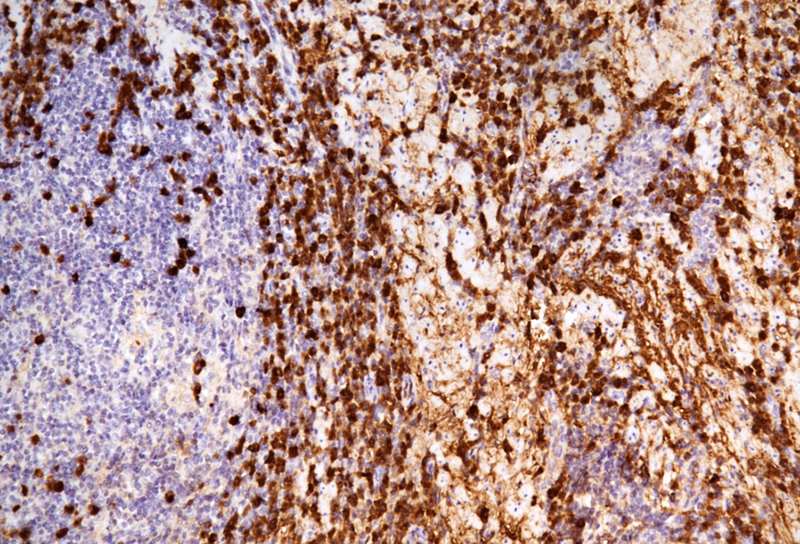

The microscopic examination of the resection specimen revealed diffuse lymphoplasmacytic infiltration throughout the oesophageal wall, with multiple lymphoid follicles and accentuation within the inner half (Panel A). On high magnification, diffuse infiltration of the overlying squamous epithelium by lymphocytes („lymphocytic oesophagitis pattern of injury”) and occasional plasma cells was observed (Panel B). The plasma cells were strongly positive for IgG and IgG4 (Panels C-D).